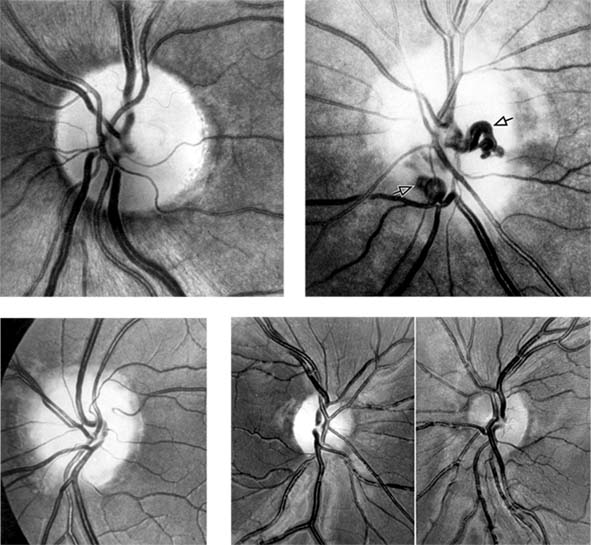

Figure 14-15

Figure 14-15: Chronic papilledema with prominent disk swelling, capillary dilation, and retinal folds but few hemorrhages or cotton-wool spots (A) and (B). Fluorescein angiography demonstrates the capillary dilation in its early phase (C) and marked disk leakage in its late phase (D).

For papilledema to occur, the subarachnoid spaces around the optic nerve must be patent and connect the retrolaminar optic nerve through the bony optic canal to the intracranial subarachnoid space, thus allowing increased intracranial pressure to be transmitted to the retrolaminar optic nerve. There slow and fast axonal transport is blocked, and axonal distention, particularly noticeable at the superior and inferior poles of the optic disk, occurs as the first sign of papilledema. Hyperemia of the disk, dilated surface capillary telangiectases, blurring of the peripapillary disk margin, and loss of spontaneous venous pulsations are the signs of mild papilledema. Edema around the disk can cause a decreased sensitivity to small isopters on visual field testing, but circumferential retinal folds with changes in the internal limiting membrane reflexes (Paton's lines) will eventually become evident as the retina is pushed away from the choked disk; when the retina is pushed away, the blind spot will be enlarged to large isopters on visual field testing as well. In acute papilledema, probably as a consequence either of markedly elevated or rapidly increasing intracranial pressure, there are hemorrhages and cotton-wool spots, indicating vascular and axonal decompensation with the attendant risk of acute optic nerve damage and visual field defects (Figure 14-14). There may also be peripapillary edema (which can extend to the macula) and choroidal folds. In chronic papilledema (Figure 14-15), which is likely to be the consequence of prolonged moderately raised intracranial pressure, a process of compensation appears to limit the optic disk changes such that there are few if any hemorrhages or cotton-wool spots. With persistent raised intracranial pressure, the hyperemic elevated disk gradually becomes gray-white as a result of astrocytic gliosis and neural atrophy with secondary constriction of retinal blood vessels, thus leading to the stage of atrophic papilledema (Figure 14-16). There may also be retinochoroidal collaterals (previously known as opticociliary shunts) linking the central retinal vein and the peripapillary choroidal veins, which develop when the retinal venous circulation is obstructed in the prelaminar region of the optic nerve. (Other causes of retinochoroidal collaterals are central retinal vein occlusion, optic nerve sheath meningioma, optic nerve glioma, and optic nerve head drusen.) Vintage papilledema is characterized by the presence of drusen-like deposits within the swollen optic nerve head.

Figure 14-16

Figure 14-16: Atrophic papilledema in a child with a cerebellar medulloblastoma. The disk is pale and slightly elevated and has blurred margins. The white areas surrounding the macula are reflected light from the vitreoretinal interface. The inferior temporal nerve fiber bundles are partially atrophic (arrows).